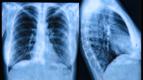

AnnonsIPF är en svår lungsjukdom som drabbar cirka 200 000 individer i västvärlden.